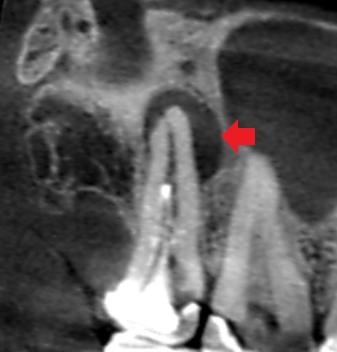

初診時の上顎第二大臼歯の冠状断のCT画像です。

赤い矢印の先の口蓋根の横に長い膿の影がみられます。歯根破折や根尖孔外感染が疑われるケースです。